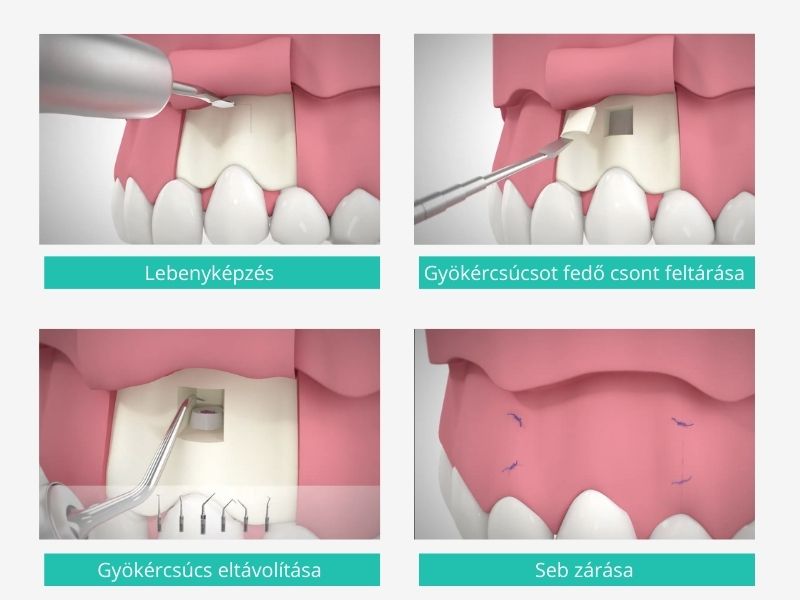

- Érzéstelenítés: a műtétet helyi érzéstelenítésben végezzük, így a beavatkozás teljesen fájdalommentes

- Lebenyképzés

- A gyökércsúcsot fedő csont feltárása

- A gyökércsúcs eltávolítása a gyulladt területtel együtt: nagyon fontos, hogy a teljes gyulladt szövetállomány eltávolításra kerüljön, máskülönben fennáll a veszélye a fertőzés kiújulásának

- Bizonyos esetekben gyógyszeres tömés alkalmazása szükséges (ún. retrográd gyökértömés) a gyökércsatorna résmentes lezárására a csúcsi részen

- Seb zárása